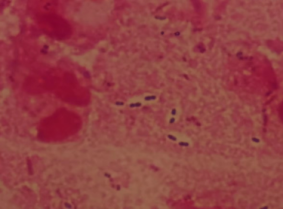

肺炎链球菌于1881年首次由巴斯德(Louis Pasteur)及G. M. Sternberg分别在法国及美国从患者痰液中分离出,为革兰染色阳性双球菌。